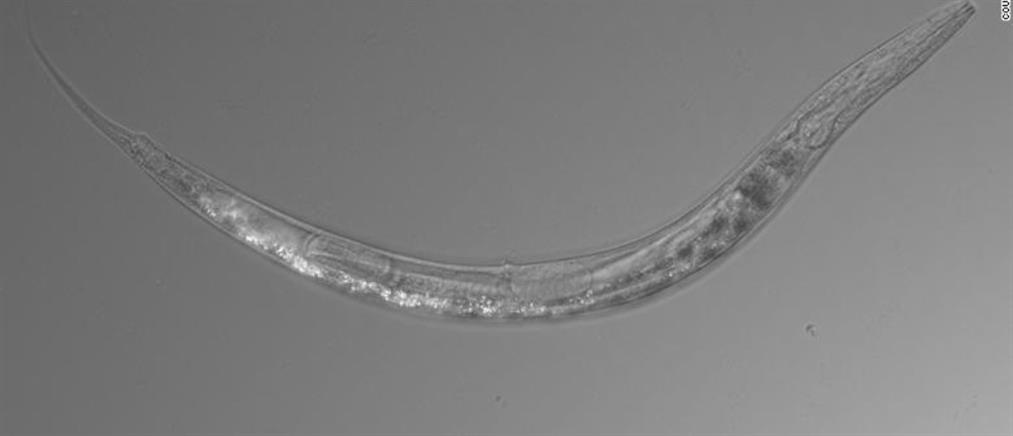

Ζωντανό σκουλήκι 8 εκατοστών βρέθηκε σε εγκέφαλο γυναίκας (εικόνες)

Αντιμέτωποι με ένα πρωτοφανές θέαμα στα παγκόσμια ιατρικά χρονικά βρέθηκαν χειρουργοί στην Αυστραλία κατά τη διάρκεια επέμβασης εγκεφάλου. Το χρονικό της υπόθεσης.